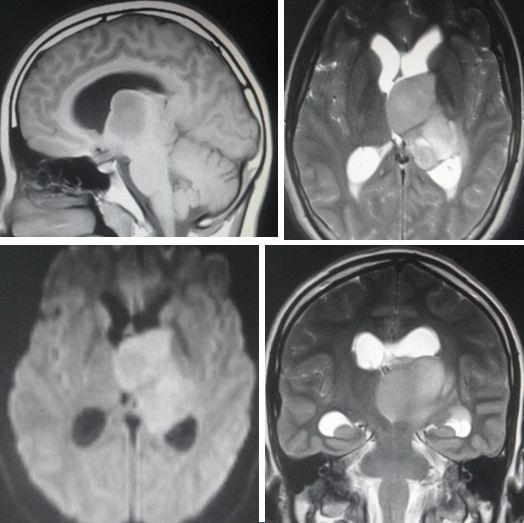

Z is a 16 plus years old girl. For the past 10 years or so, she had been having sinus problems and had been on doctor’s medication. About two months ago, August 2016, she became dizzy and had pain when moving her head. She also vomited a lot. A CT scan and MRI done showed a 35 x 30 x 30 mm enhancing mass in the region of third ventricle, at or near the left foramen of Monro.

A biopsy done the next day confirmed left thalamus tumour, features consistent with a glioblastoma, WHO grade 4.

The third ventricle is a narrow cavity that is located between the two halves of the brain. CSF flows into the third ventricle through openings in its roof called the foramen of Monroe. The two foramen of Monroe are connected to the left and right lateral ventricles above. The third ventricle is connected to the fourth ventricle below by the cerebral aqueduct (canal) of Sylvius, which passes through the midbrain.

If the channel through which this fluid flows is blocked then fluid accumulates in the brain. Hydrocephalus is a medical term that refers to an abnormal accumulation of CSF within cavities inside the brain called ventricles.